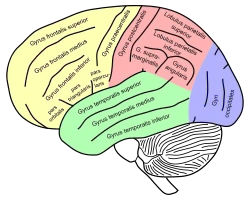

Lateral view of a human brain, main gyri labeled. Drawing of a cast to illustrate the relations of the brain to the skull. (Superior temporal gyrus labeled at center, in green section.)

Position of superior temporal gyrus (shown in red). Lateral view of a human brain, main gyri labeled.